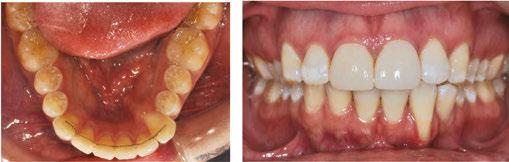

In the first case example, a 60-year-old patient, relapsed from prior orthodontic treatment, presented with an edge-to-edge bite, bilateral crossbite, and gingival recession. She had a periodontal consultation but decided to postpone surgery until after her son’s upcoming wedding. She requested a system that moves teeth more gently due to her periodontal concerns.

The doctor planned for expansion in the upper and lower arches with elastics on the first molars as well as enameloplasty for the upper-right incisor. The treatment objectives were achieved in 7 months with no worsening of her gingival recession. In addition to her periodontal status remaining stable, the patient’s primary goal of completing treatment in time for her son’s wedding was successfully met.

Figure 3: Case 1 initial records (left) and final records (right)

The next case example is a 33-year-old relapse patient who is a very busy plastic surgeon. She did not consider correcting her relapse until she heard about NiTime Aligners. She was 50% Class II and moderately crowded. The treatment plan was to level the lower occlusal plane and use Class II elastics for the right buccal segment to correct the tooth interdigitation as well as broaden the buccal segment and resolve crowding in the anterior teeth.

Case 4 (Figure 6)

Contributing clinician: Dr. Neil Warshawsky, Illinois

This 33-year-old patient was a Class I Div 2 malocclusion with a moderately deep overbite, moderate upper/ lower crowding, and retroclined incisors. She also had gingival recession on the lower canines and first premolars. She chose NiTime since she is a teacher and felt self-conscious about undergoing orthodontic treatment.

The treatment plan was to resolve her crowding through expansion with Class II elastics to procline the maxillary incisors and increase the overjet. The plan will also intrude the incisors and extrude the premolars to assist in the leveling of the case. Her treatment progress is shown at stage 28.